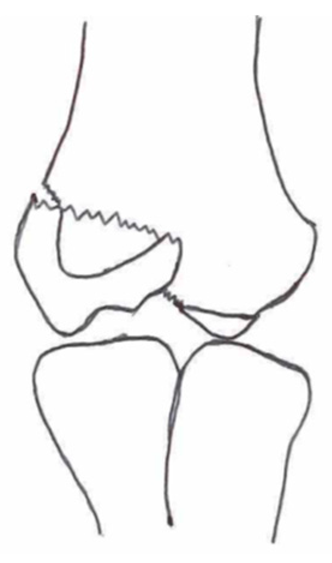

2.3. Classification of Fractures

| Classification | Type 1 (A) | Type 2 (B) | Type 3 (C) | Type 4 | Type 5 |